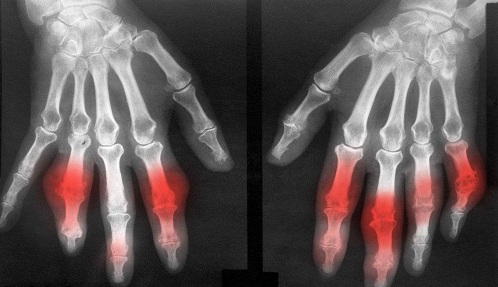

3、关节部位表现:第一次患有痛风病都会出现在第一石趾关节,单肩关节,累及到跗骨关节,踝关节,指关节的呢各地,可根据病情出现不同程度的肿痛或者是关节皮肤出现光泽暗红色。》》》在线,点击进入快速咨询、预约通道

4、检查结果:在检查的时候,鉴定为痛风不仅是根据高尿酸血症的,通过关节部位出现不对称的关节囊肿,或者是骨支质下的囊肿反应均可以鉴定为早期痛风的症状。》》》在线,点击进入快速咨询、预约通道